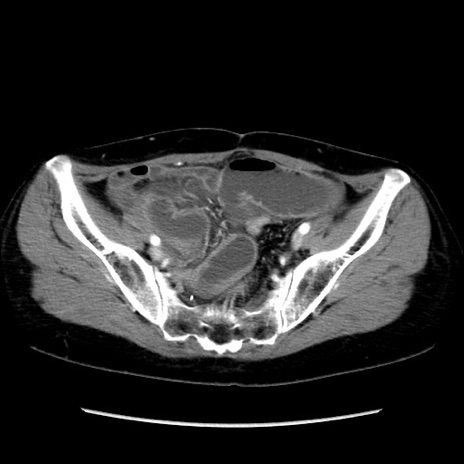

症例32(横断像)

【症例】40歳代 女性

【主訴】上腹部痛、嘔気・嘔吐

【現病歴】約9時間前頃から急に上腹部痛、嘔気、嘔吐が出現。改善しないため救急要請。

【既往歴】子宮頚癌(広汎子宮全摘術、放射線療法)、腸閉塞

【身体所見】腹部:平坦、軟、腸雑音亢進、上腹部を中心に腹部全体に圧痛あり。

【データ】WBC 8400、CRP 0.03